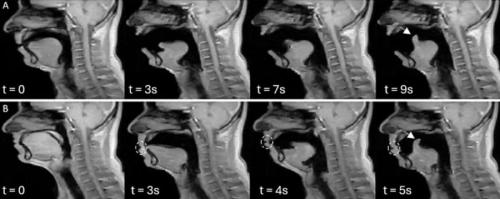

答えを得るため研究チームはまず、健康な大人を磁気共鳴画像装置に入ってもらい、「ふつうの呼吸」「口を大きく開けた深呼吸」「あくび動画を見て自然に出たあくび」「あくびをこらえたとき」の四つの動きをしてもらいました。

そのあいだに首の上の方、首の骨でいうと三番目あたりで、脳脊髄液の流れと内頸静脈を流れる血液の流れが、どの向きにどれくらいの速さで動くのかを、別々に連続的に記録しました。

もう一つの大きな発見は、「同じ人のあくびの動きが、何度くり返してもほとんど同じだった」という点です。

研究チームは、舌の先の少し後ろの部分を目印にして、その点が時間とともにどんな軌跡を描くかを計算しました。

その結果、一人の参加者の中で、別々のタイミングで出たあくび同士を比べると、その軌跡はとてもよく重なり合い、ほぼ同じ線をなぞっていることが分かりました。

数値としても、動きの似かたを表す指標がほとんどの人で高い値を示しており、なかには「ほぼ完全に一致」と言える人もいました。

さらに興味深いのは、「がまんあくび」の場合です。

参加者が口を閉じてあくびをこらえようとしても、舌の奥のほうの動きのパターンは、口を大きく開けた本物のあくびととてもよく似ていました。

外から見ると控えめなあくびでも、舌やのどの奥では「いつものあくびのプログラム」がちゃんと走っているように見えるのです。